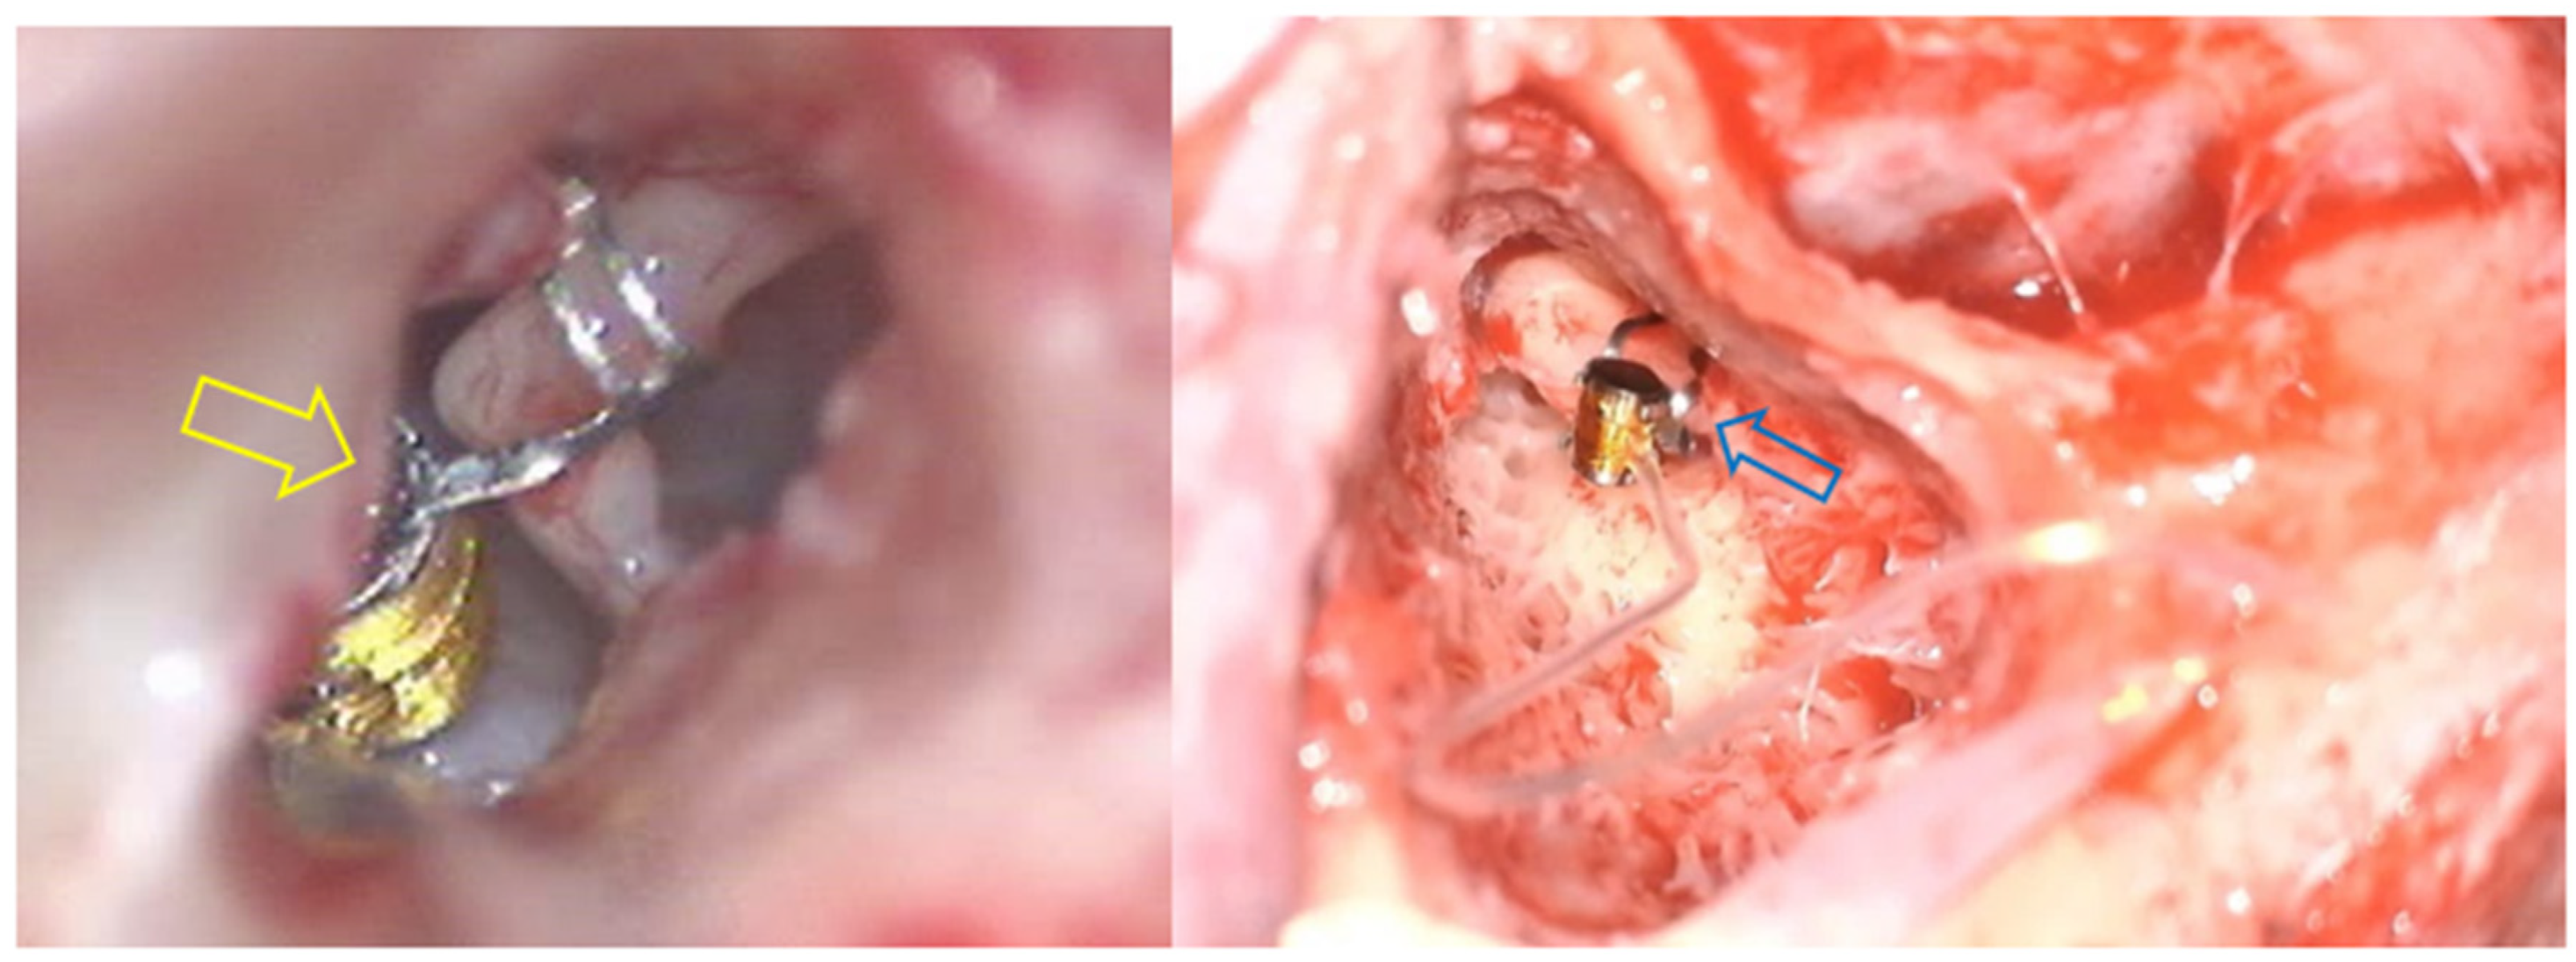

However, it is important to note that, regarding the coupling at the incus, although classically the FMT is anchored to the long process of this ossicle, in some cases, the FMT is placed on the short process of the incus through an atticotomy. Examples of different approaches to get into the incus are shown in Figure 2 [2].

Figure 2. Surgery for the placement of the VSB using two different approaches. Firstly, in the left image, the yellow arrow shows the FMT anchored on the long process of the incus through a posterior timpanotomy. In the right image, the blue arrow shows the FMT anchored also on the long process of the incus, but in this case, through an extended atticotomy.

3.2.2. Ossicular Chain Coupling

In another portion of the sample, we found a total of 14 patients in whom ossicular chain coupling was used. Specifically, in 11 of them (20%), the coupling was carried out at the incus, mainly at the long process in 81.82% (n = 9) via posterior tympanotomy, while in the remaining 18.18% (n = 2), it was performed at the short process via extended atticotomy. These differences are illustrated in Figure 1. In the remaining three patients (21.42%), the FMT was anchored to the stapes. Similarly, the same proportion of patients (21.42%) used a coupler system involving the ossicles. Out of the 14 patients, 8 of them (57.14%) had mixed hearing loss, while the remaining 42.86% (n = 6) had sensorineural hearing loss.